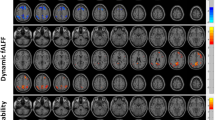

The brain activity during decision-making versus control conditions showed similar activation patterns in both T2DM and control groups (Fig. 2, Table 2). Activated regions in common included the orbitofrontal cortex (OFC), ventral medial prefrontal cortex (VMPFC), anterior cingulate cortex (ACC), dorsolateral prefrontal cortex (DLPFC), insula, parietal and occipital lobes. However, only healthy subjects showed activation within the ventral striatum and thalamus, and only T2DM patients showed activation within the posterior cingulate cortex.

Brain activation during decision-making (decision- making - control conditions). (A) Brain activation during the Iowa Gambling Task compared to its control task in the control group. (B) Brain activation during the Iowa Gambling Task compared to its control task in the T2DM group. Common activated regions included the orbitofrontal cortex (OFC), ventral medial prefrontal cortex (VMPFC), anterior cingulate cortex (ACC), dorsolateral prefrontal cortex (DLPFC), insula, parietal and occipital lobes. Only healthy subjects showed activation within the ventral striatum and thalamus, only T2DM patients showed activation within the posterior cingulate cortex. See Table 2 for details.

Statistical comparison of activation maps demonstrated that controls exhibited significantly greater activity in the OFC, VMPFC and ACC as compared to T2DM patients (Fig. 3). However, greater activity in T2DM patients, compared to controls, was observed in the right DLPFC, insula, posterior cingulate cortex and occipital lobes.